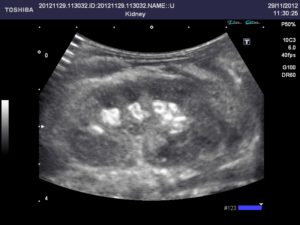

Снимок, полученный во время прохождения процедуры, может очень о многом рассказать врачу.

Ультразвуковое сканирование — недорогое и удобное обследование для диагностики мочекаменной болезни. Фото, сделанное в ходе процедуры, позволяет зафиксировать:

- наличие камней любого объема;

- их форму;

- изменение паренхимы почек;

- размеры конкрементов;

- их число.

Кроме того, эхограмма дает возможность увидеть мельчайшие образования и даже песок. Подобные данные очень важны, так как вовремя не диагностированная мочекаменная болезнь способна приводить к самым тяжелым последствиям.

Рассмотрим детальнее, как диагностировать камни в почках, если используется метод ультразвукового скрининга. Во время осмотра о наличии конкрементов говорит структура, характеризующаяся как гиперэхогенность, а также обладающая акустической тенью, размер ее должен быть не больше четырех миллиметров.

В некоторых ситуациях оксалаты, которые в диаметре имеют примерно 8-10 мм, могут не оставлять акустической тени. На УЗИ камень почки маленького размера, если используется цветовое доплеровское картирование, будет выражаться в виде артефакта мерцания позади.